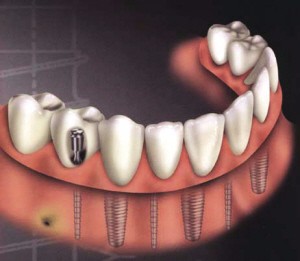

种植牙也叫人工牙齿种植,并不是真的种上自然牙齿,而是通过医学方式,将与人体骨质兼容性高的纯钛金属经过精密的设计,制造成类似牙根的圆柱体或其他形状,以外科小手术的方式植入缺牙区的牙槽骨内,经过 1~3 个月后,当人工牙根与牙槽骨密合后,再在人工牙根上制作烤瓷牙冠。